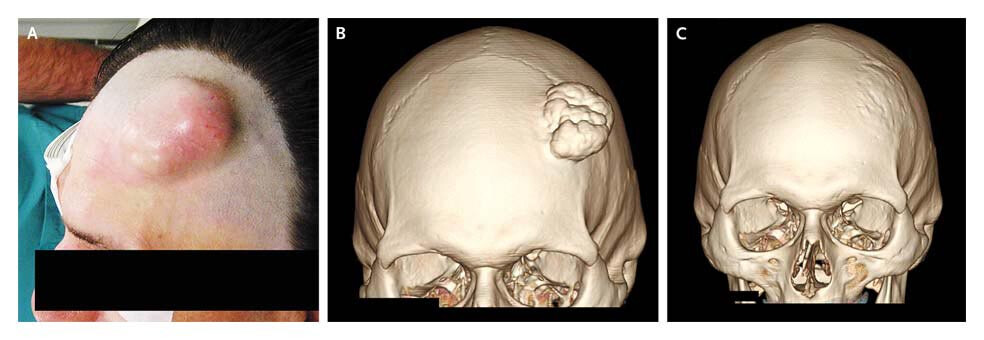

血腫後に石灰化した事例(一番右は治療後)、New England Jounal Of Medicineより引用